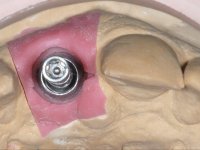

After performing an impression of the implant and making the models, we tested several rehabilitative options with the help of the implant brand planning kit. None proved capable. In this sense and as a resource solution, an innovative solution was proposed. It was proposed to make a milled Zr abutment with an appropriate design to receive a veneer that would hide the screw access hole. The veneer itself had a ceramic-coated Zr infrastructure. The goal was to achieve retention and strength by screwing the abutment and aesthetically solve the case with the veneer.

After the impression of the implant using a double-mix technique with double viscosity and the collection of shape and color information by the ceramist, we proceed with the work. In the model, a syn octa was placed over the implant, and a screw was placed on it to assess its emergence in relation to the incisal edge. Then, an adequate emergence profile in the artificial gingiva was prepared. A abutment with characteristics suitable for overbite and simultaneously capable of receiving a veneer was waxed on top of this scenario. This waxing gave rise to the manual milling of a very personalized abutment. An infrastructure in Zr was also made for the veneer with a very great adaptation to the abutment. On this infrastructure ceramics were placed. Ceramic fluorescence sought to compensate for the lack of fluorescence that Zr had and obviously further customize the aesthetics. The adhesive bridge was removed and the definitive work was placed. The syn octa was initially tightened with 35 N to the implant and then the Zr abutment was tightened over the syn octa with 15 N. The access hole was plugged and then the veneer was cemented with resin-reinforced glass ionomer. After 15 years, the patient returned to the consultation with tooth mobility. Fortunately, nowadays we have the possibility of having dynamic tightening wrenches that allow tightening screws with greater inclinations. An access cavity was made without damaging the incisal edge of the veneer. Tightening was done with a dynamic wrench with 15 N torque. The hole was covered with Teflon and filled with composite resin. This solution allowed the problem to be solved in a simple and economical way.